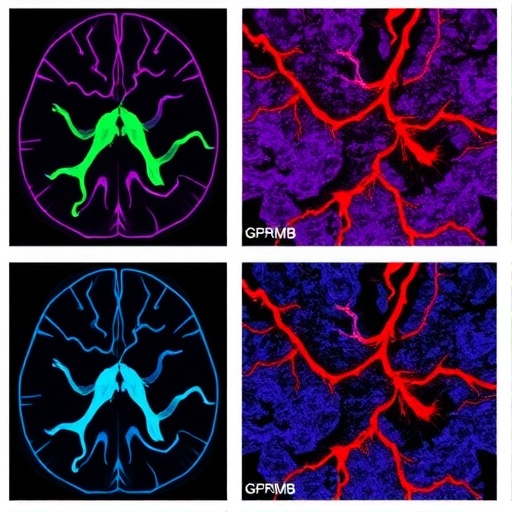

In a groundbreaking study, a research team led by Du, Long, and Li has unveiled the intricate relationship between spatially-reprogrammed GPNMB+ macrophages and COL6A3+ fibroblasts in the context of vascular fibrosis associated with glioblastoma. This research, featured in the prestigious journal “Genome Medicine,” sheds light on the cellular interactions that exacerbate tumor progression in one of the most aggressive forms of brain cancer.

The study identifies GPNMB+ macrophages as pivotal players in the tumor microenvironment. These cells are derived from the reprogramming of monocytes and exhibit distinct phenotypic and functional characteristics that contribute to the fibrotic milieu surrounding the tumor. The spatial reprogramming of these macrophages is triggered by the local cues provided by the glioblastoma microenvironment, driving their transformation into a pro-fibrotic phenotype.

Importantly, the interaction between GPNMB+ macrophages and COL6A3+ fibroblasts plays a critical role in enhancing vascular fibrosis. COL6A3, a collagen type often associated with tissue repair and fibrosis, is secreted by fibroblasts and contributes to the structural integrity of the tumor microenvironment. The study reveals that GPNMB+ macrophages promote COL6A3 expression in fibroblasts, thereby amplifying the fibrotic response and facilitating tumor growth.

Article Title: Spatial-reprogramming derived GPNMB+ macrophages interact with COL6A3+ fibroblasts to enhance vascular fibrosis in glioblastoma.